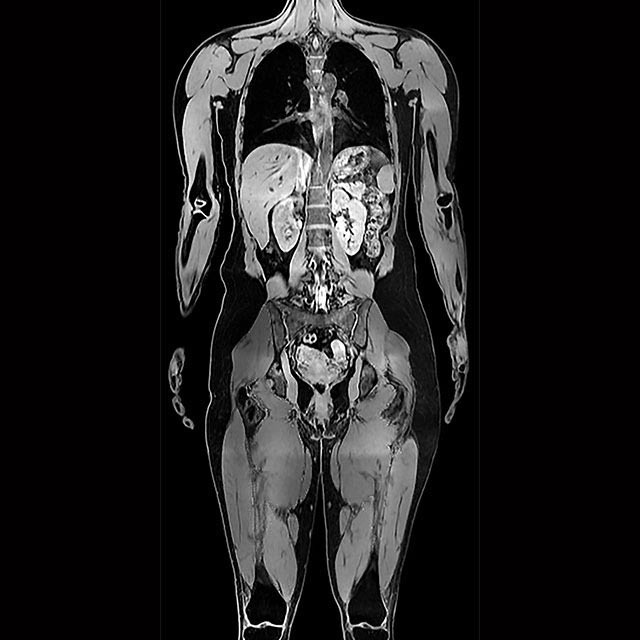

The AMRA® BCP Scan is a neck-to-knee MRI-based service using our validated protocols for creating an individualized Body Composition Profile (BCP). After we analyze the images, you receive an easy-to-interpret report containing precise body composition measurements with comparison to normative values.

Rapid, Neck-to-knee MRI

Image multiple areas of the body within a single scan, send those images to us for analysis, and get muscle and fat measurements with comparison to normal ranges.